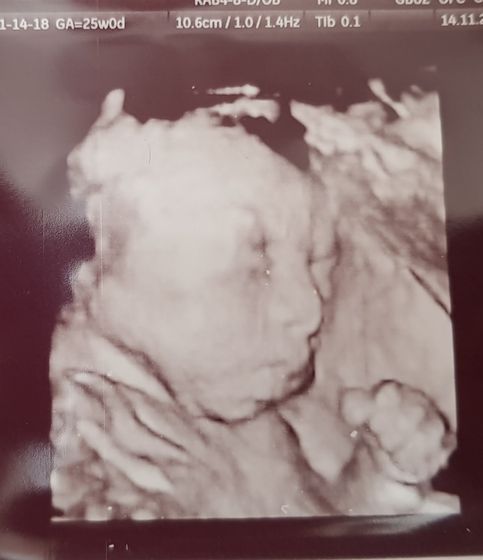

Предыстория: муж мой тут загулял с друзьями и видимо подзабыл, что жена беременна. Небольшой скандал, мои конченные нервы и как итог тонус, но он не был сильным. Он все это увидел дело, запереживал естественно, да и я для пущей страсти жуть гнала, говорю «Завтра на УЗИ едем, переживаю я». Он ни разу не ходил со мной до этого. Приехали меня зовут значит, говорю идём со мной.Глаза его были полны страха, но зашел тут все так весело начинают врачи шутить делать фоточки, фото было в 3Д. А, там то ручка, то ножка, то зевнет, то моргнет ну вообщем я была против узи в 3д, 6д итп, мне казалось это страшным.Я изменила свое мнение на 1000%%%, внимательно рассмотрели на кого похожа.Муж сидит молчит (к слову он очень любит пошутить и я переживала, что буду от его шуток нервничать). Отдали фото, говорят в другой кабинет теперь УЗИ и доплер, он такой завис в коридоре, а врач нет-нет папаша с нами. Все в норме, показали вплоть до глаз малышки, выходим врач ему: Ну как? Ответ: это страшнее, чем с парашютом прыгать. Вышли интересуюсь чего ж так боялся? Я говорит, только и ждал когда после каждого измерения говорят:«В норме», это так страшно, у меня сердце чуть не вышло. Ну, и всю дорогу причитания, что уже скоро, уже коляску надо купить, она уже большая, а когда родишь то скоро совсем, время бежит, нос у дочки красивый и все все дела. Девочки берите мальчиков на УЗИ!!! впечатлений на всю жизнь!!!

Мы три раза ходили.Наш папа потом с фотками этими не расставался-говорил мне 'А хочешь я тебе дочь свою покажу.Правда, она у меня красавица'))Хотя скупее на эмоции человека я не встречала))